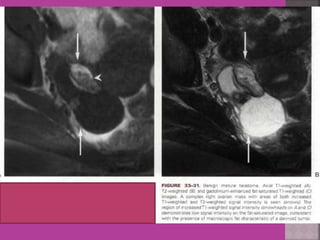

Degeneration Of Fibroid

Cystic Degeneration of

Fibroid